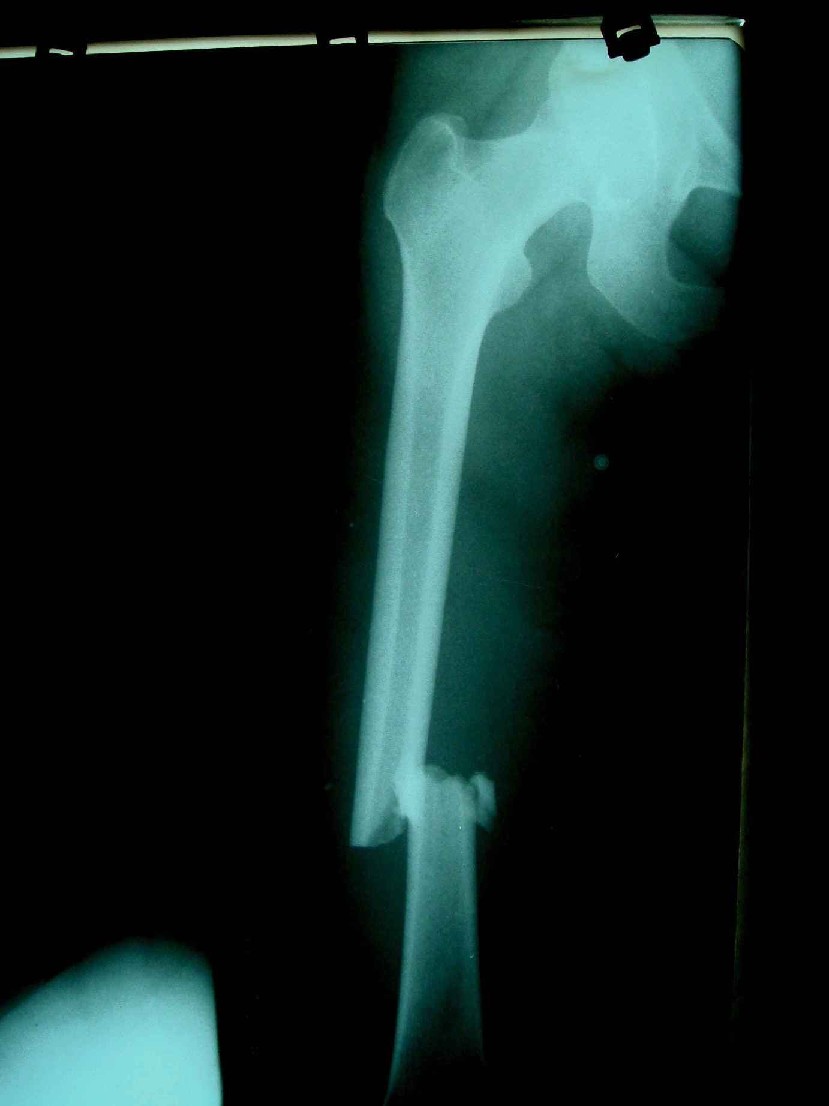

患者,女,因外伤就诊。摄骨盆及右股骨。当时报告骨盆未见明显异常,右股骨中段粉碎性骨折。五天后行股骨中段骨折内固定手术,术中摄床边片示股骨颈骨折。现把术前和术中图像上传。请大家高诊,分析股骨颈骨折是术前漏诊还是其他原因。术前骨盆片右股骨颈显示欠佳是由于股骨中段骨折无法将股骨颈完全显示。

现在我向大家请教,股骨中段粉碎性骨折的同时股骨颈也会骨折吗,另外如图所示该患者股骨颈骨折线是我们常见的由外伤引起的骨折线吗。

术前片示右股骨颈未见明显骨折征象。如果事先有骨折,由于投照位置原因,骨折线也是完全有可能被挡住重叠而看不见的(并且本例骨折对位良好,更有可能看不到)。所以要凭此判断述前是否有骨折不容易

术前所照的片子体位好象有点不标准,右侧股骨颈显示不是很好,没有完全展开,所以不好说术前就一定没有骨折的情况.